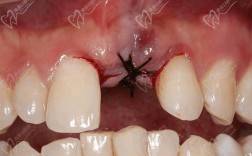

- 手术创伤刺激:种植过程中,术区需切开牙龈、剥离骨膜、制备种植窝,甚至可能进行骨增量(如植骨),这些操作会损伤局部小血管和淋巴管,导致组织液渗出,引发肿胀。

- 术中微创操作:选择经验丰富的医生,采用微创种植技术(如数字化导板种植),减少组织损伤和手术时间。